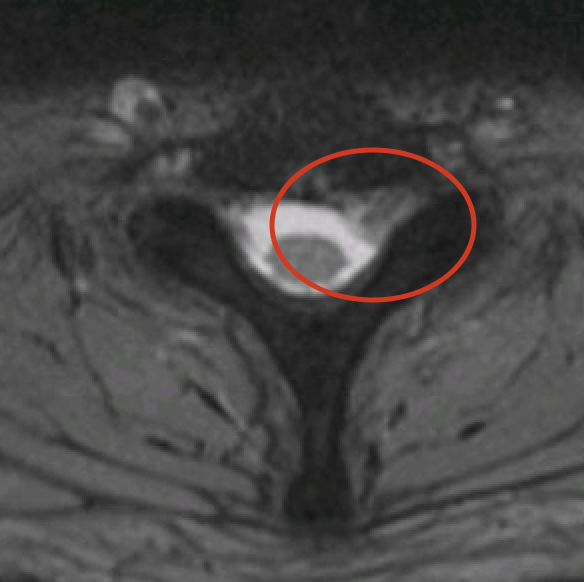

Het ideale onderzoek is een NMR (=MRI). Het levert ons de beste beelden en gebruikt geen nadelige X-stralen. Soms wordt ook een CT scan van de nek gevraagd.

Discus hernia betekent in het Nederlands breuk (= hernia) van de tussenwervelschijf (= discus). Een tussenwervelschijf bestaat immers uit een centraal zacht gedeelte en een omliggende ring. De breuk ontstaat in de buitenste ring waardoor het zachte gedeelte naar achter schuift en druk geeft op het ruggenmerg of zenuwen. Hierdoor kan pijn in de arm ontstaan. Een hernia kan ook aanwezig zijn zonder symptomen en moet dan ook niet verder behandeld worden.